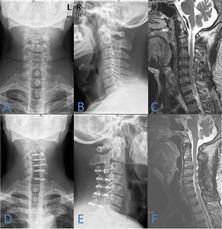

To explore the factors associated with the increased spinal cord area in single-door cervical laminoplasty (SDCL) with miniplate fixation.

A retrospective study enrolled 83 patients underwent SDCL with miniplate fixation and the patient characteristics such as age, gender, tobacco use, alcohol use, diabetes mellitus, hypertension, diagnosis, operative level, etc., were obtained. The opening angle, door shaft position and spinal canal area of the patients were measured after surgery. The sagittal canal diameter (SCD), the C2-7 Cobb angle, the cervical curvature index (CCI), the range of motion (ROM) and the spinal canal area were measured before and after operation. The increased cervical spinal cord area was also measured before and after surgery, and the correlation between the above indicators and the increased cervical spinal cord area was studied through Pearson's correlation analysis and multivariate logistic regression analysis.

There were 34 patients in small spinal cord area increment group (SAI group), 29 patients in middle spinal cord area increment group (MAI group) and 20 patients in large spinal cord area increment group (LAI group). The preoperative diagnosis(P = 0.001), door shaft position (P = 0.008), preoperative spinal canal area (P = 0.004) and postoperative spinal canal area (P = 0.015) were significant different among the 3 groups. The multivariate analysis showed that the preoperative diagnosis (OR = 2.076, P = 0.035), door shaft position (OR = 3.425, P = 0.020) and preoperative spinal canal area (OR = 10.217, P = 0.009) were related to increased spinal cord area.

The preoperative diagnosis, door shaft position and preoperative spinal canal area might be associated with increased spinal cord area after cervical laminoplasty with miniplate fixation. Preoperative symptoms are mostly caused by compression of the spinal cord, so spinal cord area enlargement can bring a better recovery in patients alongside long-term. Spine surgeons should pay more attention to the accuracy of the preoperative diagnosis, the preoperative measurement of spinal canal area and the door shaft position during the operation.